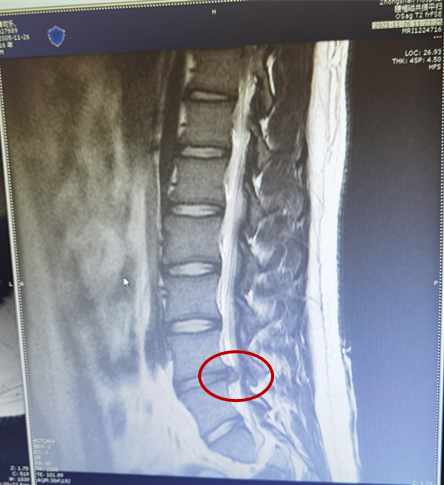

11月30日,抱着最后一丝希望,夫妻俩带着儿子找到了91porn 疼痛科一病区主任王云霞。王主任仔细为患者查体、询问病情,结合核磁共振的结果,王主任判断小王的腿痛是腰椎间盘突出引起的,因为突出有点大,最佳的治疗方案是微创内镜手术。看到李女士的犹豫和担心,王主任对着腰椎片子耐心地解答道:“腰椎间盘突出根据突出的大小、部位及患者的症状可以选择保守治疗和手术治疗,每个患者都有最适合的治疗方案”。“可是他这么小就手术,我还是很担心,会不会不好恢复啊。”李女士仍旧放心不下。

小王的椎间盘突出物

王主任表示,孩子虽只有15岁,但椎间盘突出较大,腿痛腿麻影响睡眠,保守治疗效果不好,如此突出物自行吸收可能性不大,通过微创手术拿出突出物,孩子的腿痛腿麻就会立竿见影好转。王主任介绍,随着科技的进步,腰椎间盘突出症已不再需要传统开刀手术了,这次治疗选择的椎间孔镜微创手术,是在局部麻醉下,经皮穿针经过人体自然孔道椎间孔到达椎间盘突出位置,在内镜明视下清楚的看到神经根与突出物的关系,精准摘除椎间盘突出物,保留有用的椎间盘,达到解除神经根压迫、消除疼痛的效果。整个过程几乎无出血,仅有一个6毫米的小孔,保护了脊柱结构的稳定性不受影响,患者术后24小时即可下床活动。因为损伤小,又是局部麻醉,目前可以说是治疗包括高龄老人、年轻人患腰椎间盘突出症、腰椎管狭窄症的最佳手术方式。